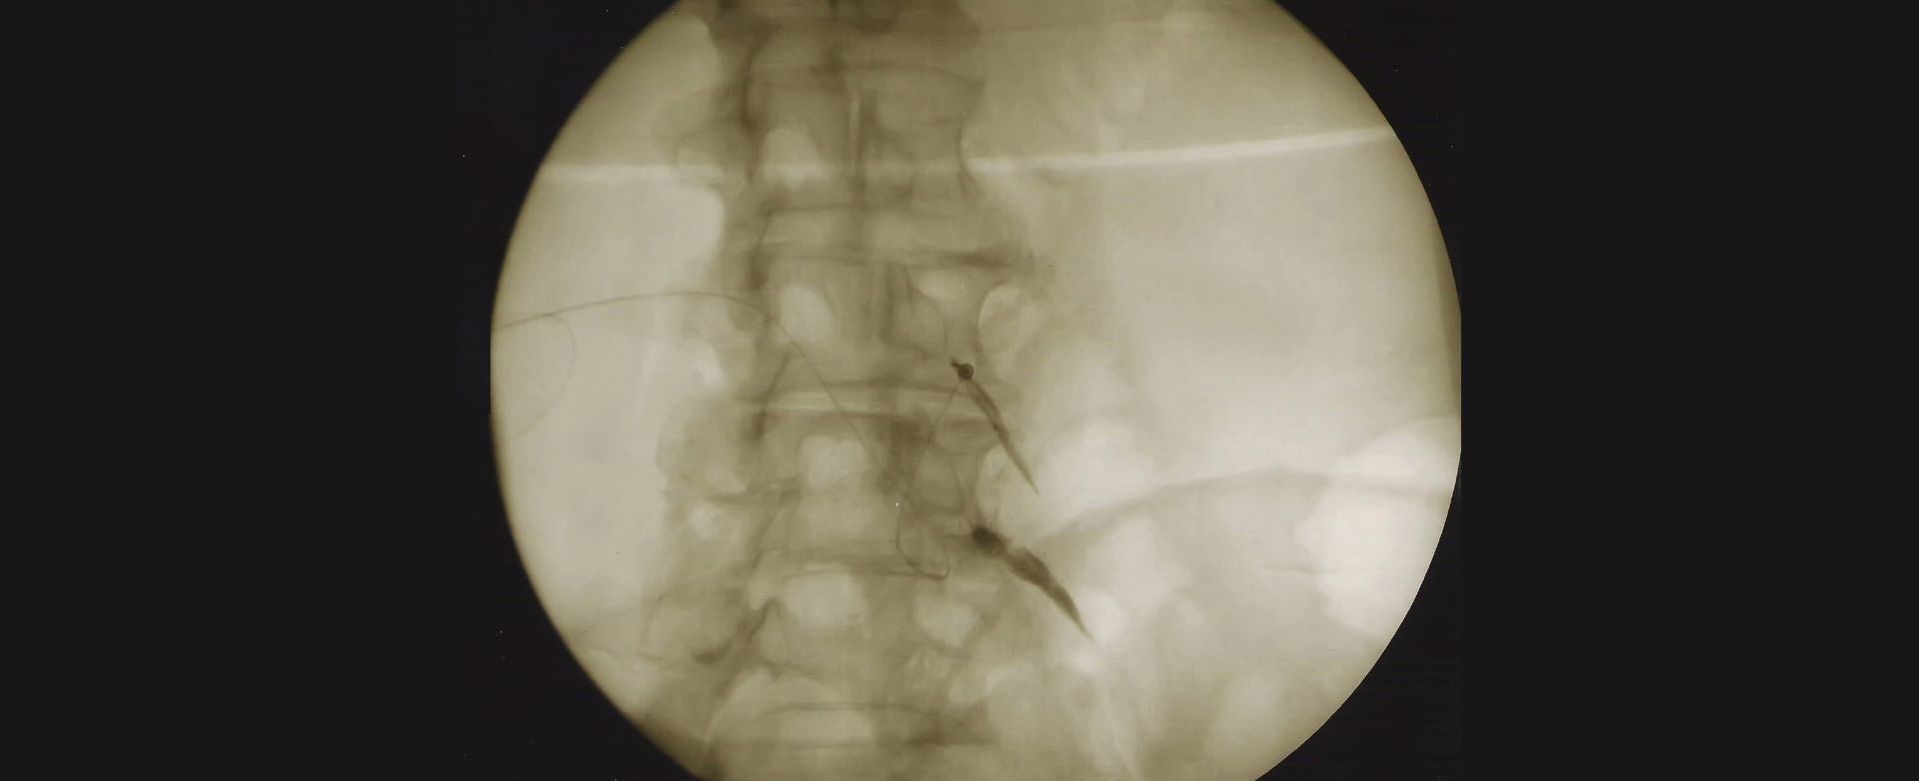

Ο ασθενής τοποθετείται σε πρηνή θέση και βρίσκεται σε ενσυνείδητη ελαφρά καταστολή. Μετά από λοξή ακτινοσκοπική λήψη περίπου 20 μοιρών, σημαδεύεται με ακτινοσκιερή μεταλλική λαβίδα στο δέρμα, το σημείο εισόδου της βελόνας, που αντιστοιχεί στο πλάγιο όριο του σώματος του σπονδύλου κάτω από την εγκάρσια απόφυση. Μετά από τοπική αναισθησία στο σημείο εισόδου και βαθύτερα στην πορεία της προώθησης της βελόνας, εισάγεται βελόνα ραχιαίας με κυρτό άκρο, η οποία προωθείται αργά υπο ακτινοσκόπηση μέχρι να έρθει σε επαφή με το σώμα του σπονδύλου. Στο σημείο αυτό η ακτινοσκοπική λήψη μεταβάλλεται σε πλάγια θέση. Το άκρο της βελόνας προωθείται ελαφρώς πιο μπροστά από το πίσω όριο του σπονδυλικού σώματος σε επαφή με αυτό. Χορηγείται 0,5 ml σκιαγραφικής ουσία και λαμβάνεται προσθιοπίσθια και ξανά πλάγια λήψη για την επιβεβαίωση της σωστής θέσης της βελόνας και στη συνέχεια χορηγείται 1ml τοπικό αναισθητικού μακράς διάρκειας δράσης για τον εκλεκτικό αποκλεισμό του αναστομωτικού κλάδου. Για κάθε επώδυνο δίσκο ο αποκλεισμός γίνεται στο επάνω και κάτω από το δίσκο σπόνδυλο, αμφοτερόπλευρα.